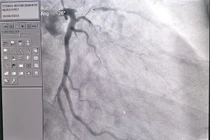

Một thuyền viên trẻ quốc tịch người nước ngoài bị nhồi máu cơ tim cấp đã được các bác sĩ Bệnh viện Đa khoa tỉnh Quảng Ninh can thiệp đặt stent cấp cứu thành công, giúp bệnh nhân thoát khỏi cơn nguy kịch.

Không khó thở, tức ngực hay bị bệnh tim, tình cờ khám sức khỏe phát hiện hẹp khít động mạch vành. Bệnh là một trong những nguyên nhân gây tử vong và nằm viện kéo dài hàng đầu. Nguyên nhân thường gặp hút thuốc lá, thuốc lào nhiều năm.